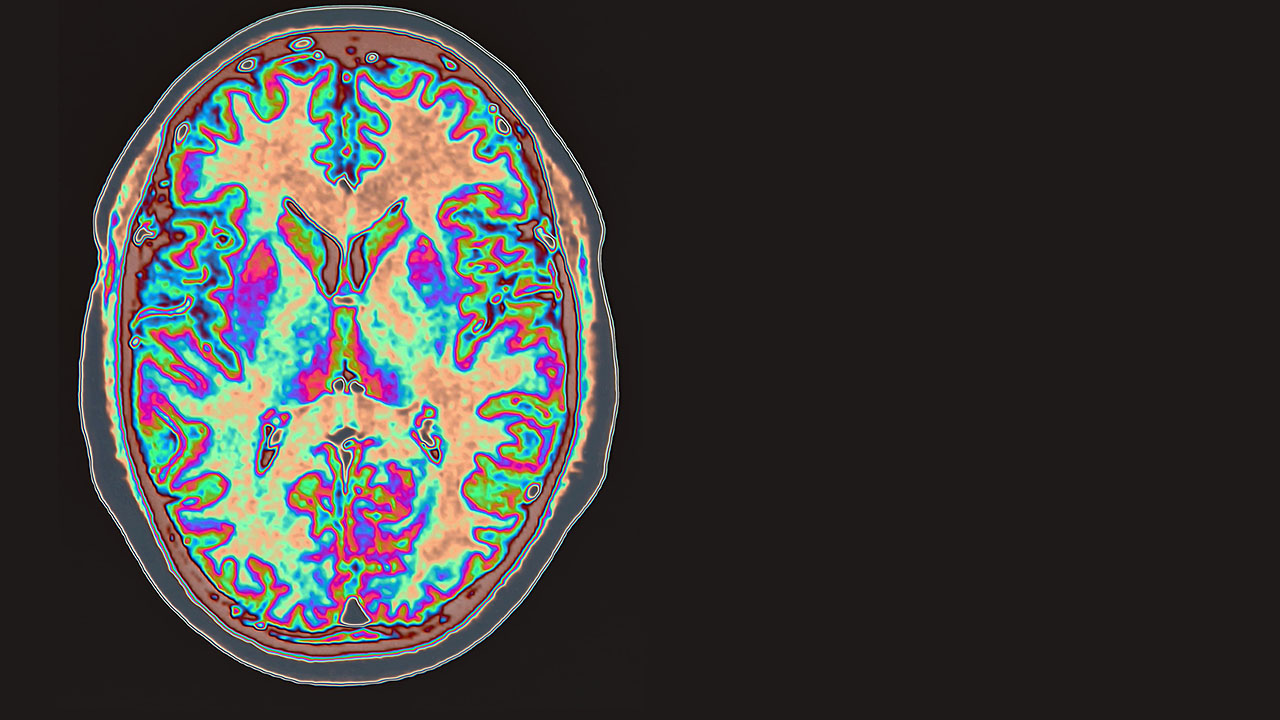

When the Immune System Attacks the Brain

What Is Autoimmune Encephalitis?

Your immune system protects you. It detects germs that could make you sick and attacks them with antibodies. In autoimmune diseases, your immune system attacks a part of your body by mistake. In rheumatoid arthritis, the immune system attacks the joints. In inflammatory bowel disease, the immune system attacks the gastrointestinal tract. In autoimmune encephalitis (AE), the immune system attacks the brain.